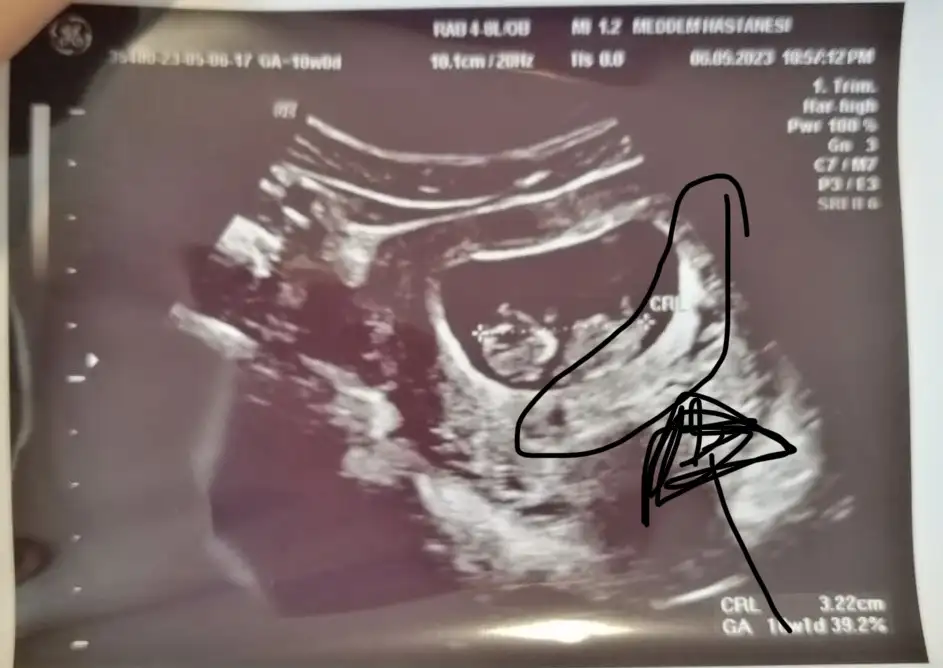

Bugün tam 10 haftalık karından plasentayı da çizdim doktor söyledi orası olduğunu tahminini bekliyorumBurada kaç haftalık? Parlak alan solda gibi eğer karından ultrason ise erkek diye anlıyorum :)

10 haftalık karından bi tahmin alabilir miyiz lütfeeeeenMaşallahsanırım 9 haftalık bana kız gibi geldi ama tamamen öylesine his